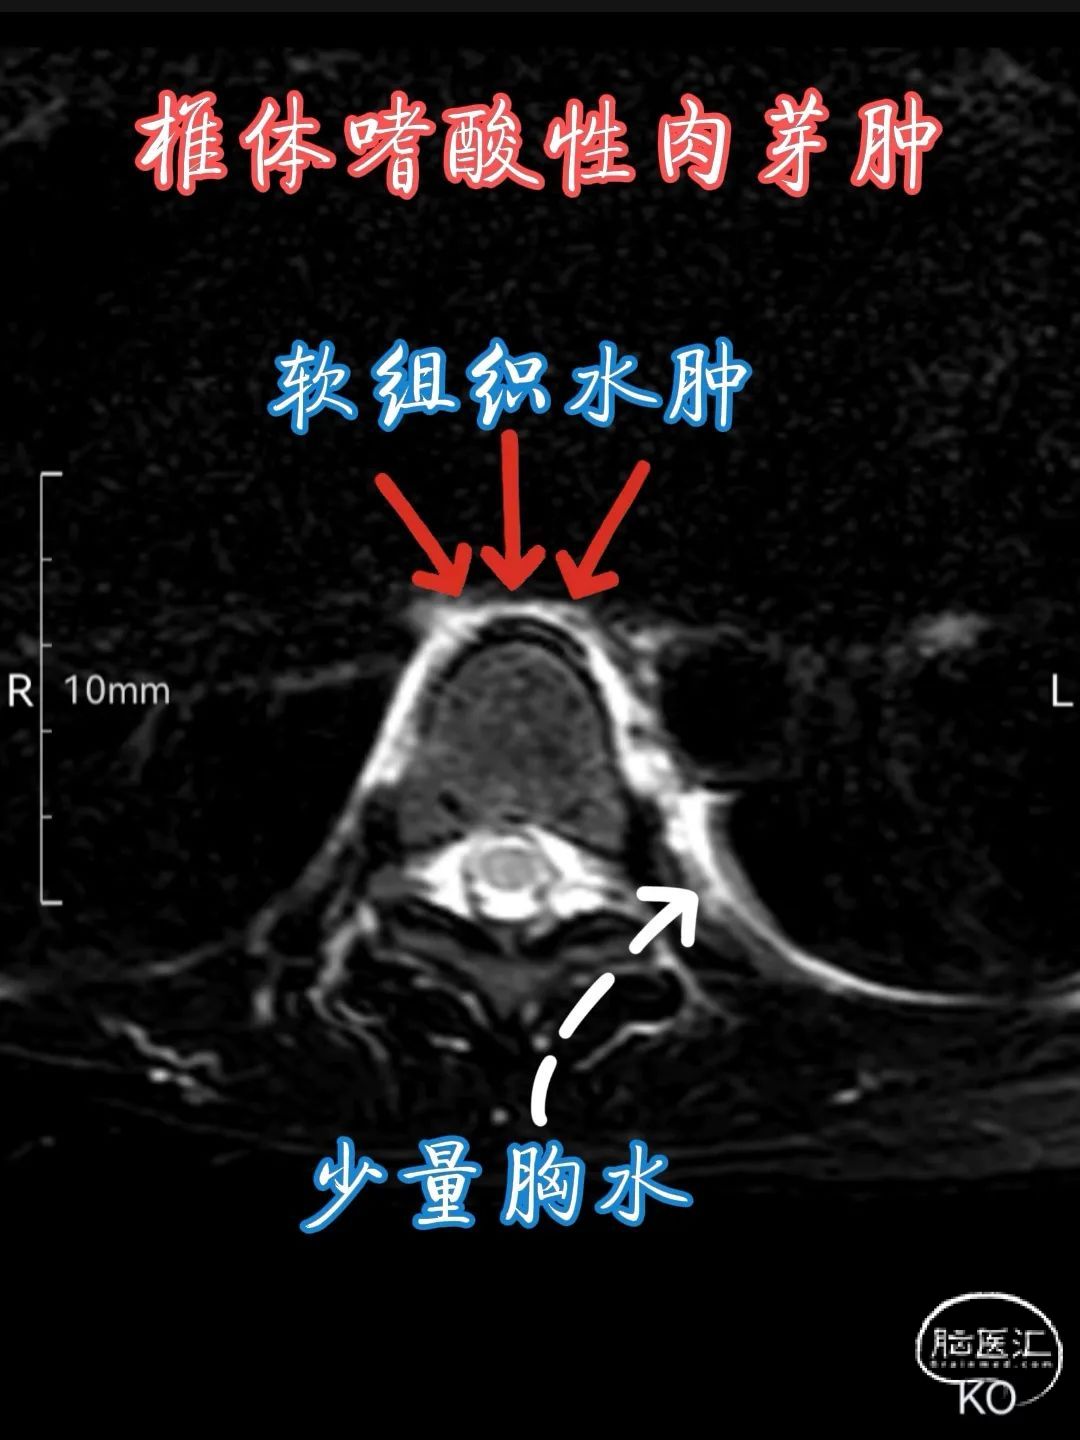

•MRI 检查 :MRI 对于检测椎体嗜酸性肉芽肿具有较高的敏感性,能够清晰地显示病变的范围、部位、形态以及与周围组织的关系。在 T1 加权像上,病变通常呈低到中等信号强度,与正常骨髓相比信号较低;在 T2 加权像上则呈高信号强度,这是由于病变组织内含有较多的水分和黏多糖等成分。此外,MRI 还可显示病变周围的软组织水肿、炎症反应以及神经受压等情况,对于判断病情和制定治疗计划具有重要价值。